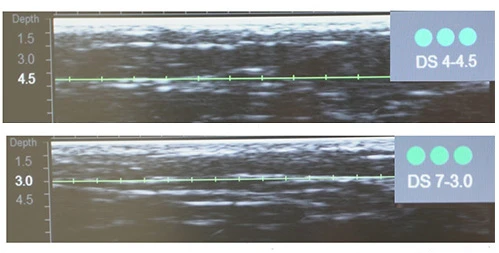

Диагностическая визуализация щёчной, периоральной и периорбитальной зон. Протокол лечения: DS 7–4,5 70 линий; DS 7–3,0 402 линии; DS 10–1,5 192 линии. Суммарно все лицо: 850 линий.

Диагностическая визуализация субментальной зоны. Протокол лечения: DS 4–4,5 97 линий; DS 7–3,0 110 линий. Суммарно все лицо, включая субментальную зону: 871 линия.